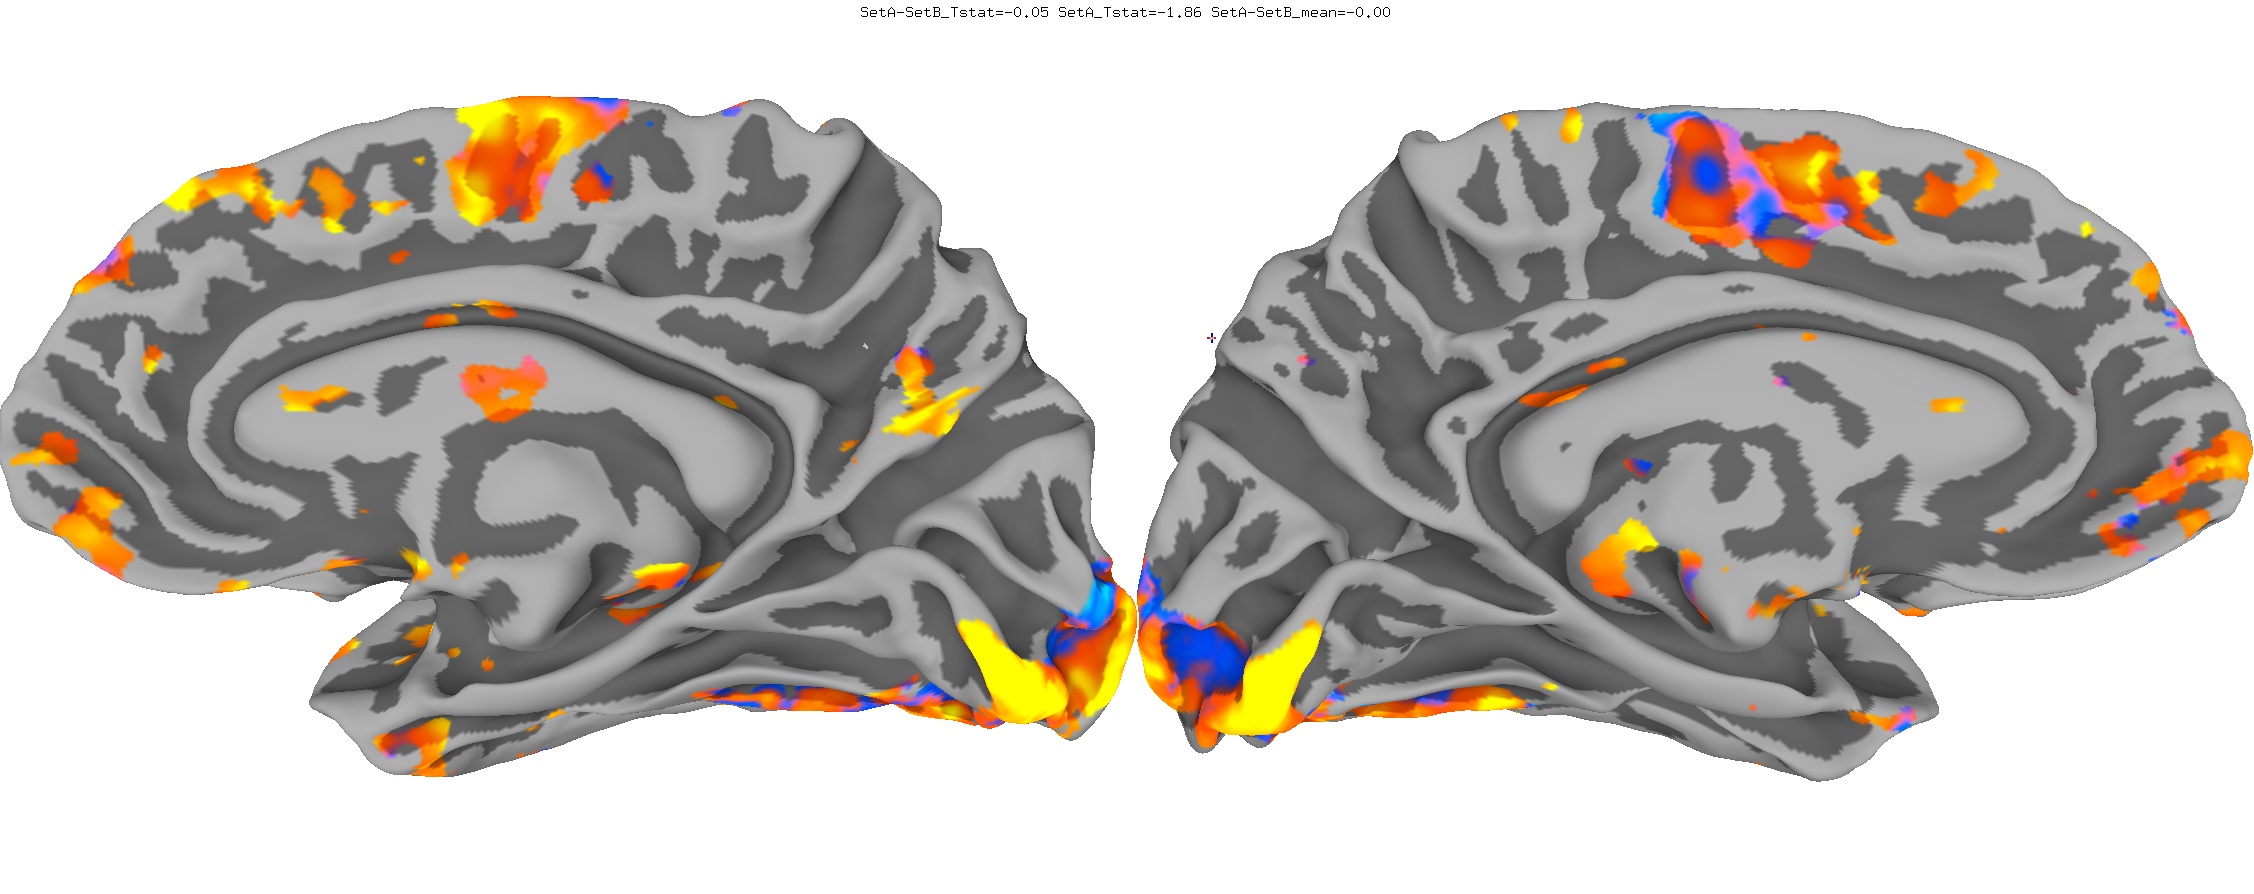

Functional Data

Functional data of the Mouth vs. Eye contrast mapped to the average surface. It is hard to quantify the difference, but one way is to compare the maximum statistical values; with better intersubject alignment, these would presumably increase.

- NEW: Max t-value for Mouth: 9.3 Eye:10.1 Eye vs Mouth: 5.6

- OLD: Max t-value for Mouth: 7.9 Eye:8.8 Eye vs Mouth: 5.8

New

Old